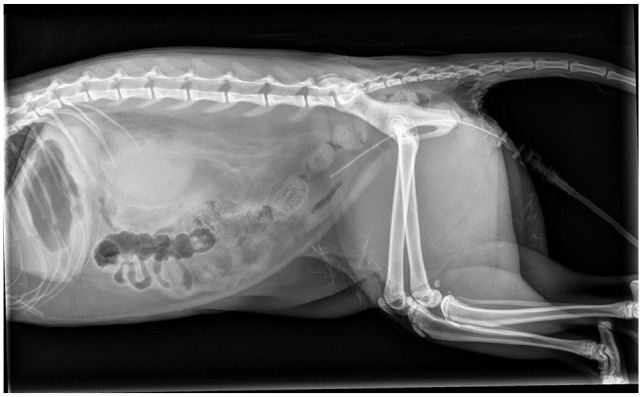

病例总结:一只8个月大的雄性家短毛猫因急性奇异尿症、大便尿症和发声而被报道。患者被诊断为尿道梗阻并住院治疗。出院后36小时,猫开始排出严重的出血性尿,并被诊断为尿腹膜和尿腹膜后。腹部超声和透视逆行阳性对比膀胱输尿管造影未发现尿路破裂的来源。剖腹探查发现双肾漏尿,伴肾盂及肾实质破裂。怀疑无菌肾盂肾炎合并肾出血导致双侧输尿管梗阻,继发尿后腹膜,延伸至尿腹膜。左侧输尿管肾切除术和右侧输尿管皮下旁路置入术作为挽救术;然而,由于预后不良,术中选择安乐死。相关性和新信息:肾盆腔和肾实质破裂是猫尿腹的一个很少报道的原因。此外,虽然严重的肾出血尚未在猫中被描述,但它可能导致双侧输尿管梗阻和尿腹。

Case summary: An 8-month-old male castrated domestic shorthair cat was presented for acute stranguria, pollakiuria and vocalization. The patient was diagnosed with urethral obstruction and hospitalized for medical management. At 36 h after discharge, the cat started passing severely hemorrhagic urine and was diagnosed with a uroperitoneum and uroretroperitoneum. An abdominal ultrasound and fluoroscopic retrograde positive contrast cystourethrogram did not identify a source of urinary tract rupture. An exploratory laparotomy revealed urine leakage from both kidneys, with evidence of rupture involving both the renal pelvis and parenchyma. It is suspected that sterile pyelonephritis and renal hemorrhage resulted in bilateral ureteral obstruction, and subsequent uroretroperitoneum, extending to cause uroperitoneum. Left ureteronephrectomy and right subcutaneous ureteral bypass placement was offered as a salvage procedure; however, euthanasia was elected intraoperatively because of a poor prognosis.